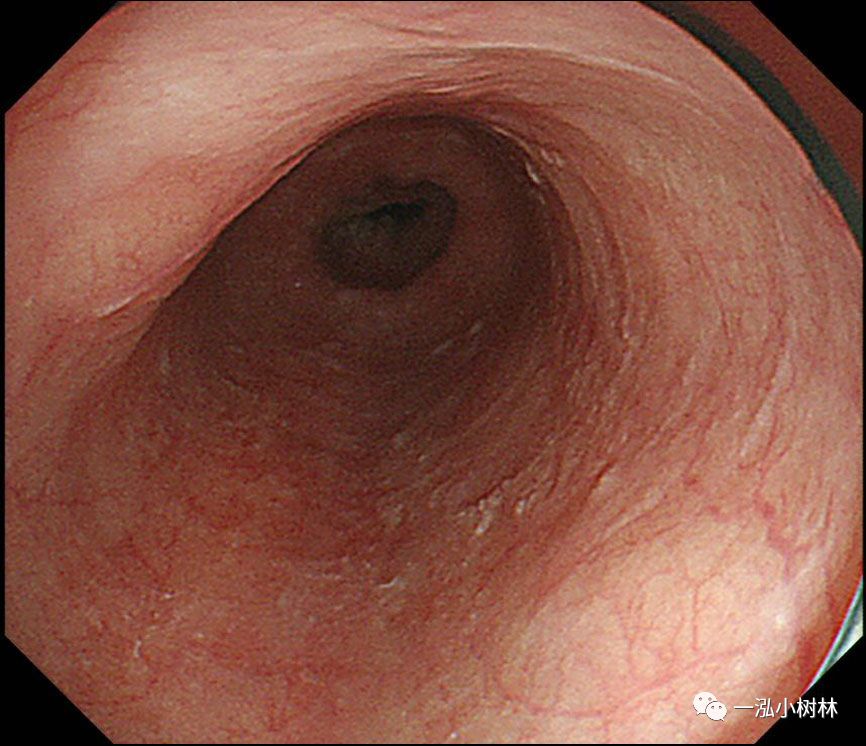

图1 白光内镜:食管中段后壁可见50mmIIb病变。